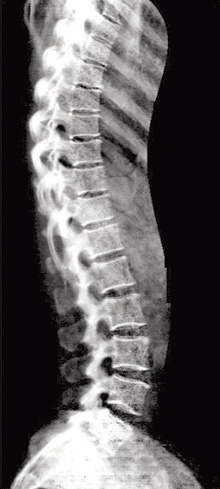

أجهزة قياس كثافة العظام Lunar IDXA بشكل عام لها دور مهم في التنبؤ المبكر للمريض بإمكانية الإصابة بهشاشة العظام. والتكنولوجيا الطبية بهذا الجهاز أسهمت في تسهيل مهمة التشخيص وإراحة المريض من خلال جهاز Lunar IDXA لقياس كثافة العظام، فهو جهاز متعدد الأغراض يستخدم في عديد من الحالات ويوفر عديدا من المميزات وهي قياس كثافة العمود الفقري من الجهتين الأمامية والجانبية وقياس كثافة عظم الفخذ الواحد وكذلك الفخذين معا وعظمة الورك والعنق وعظم الساعد إضافة إلى قياس كثافة العظم لكامل الجسم.

تقييم شامل لمكونات الجسم

يمكن لجهاز Lunar IDXA عمل أشعة عادية للعمود الفقري من الجهات الأمامية والجانبية لاكتشاف الكسور المرافقة للهشاشة دون الرجوع إلى أجهزة أشعة أخرى، وإمكانية التقييم المتقدم للورك مثل طول الورك وزاويته وأيضاً تقييم سمك فقرات العمود الفقري في حالات الهشاشة، وكذلك فإنه يتميز بقدرته على عمل تقييم شامل لمكونات الجسم من الدهون والعظام والعضلات ما يفيد في حالات السمنة والسكري ويساعد إخصائيي التغذية على معالجة ومتابعة مرضاهم على أكمل وجه.

يعطي الجهاز صورة كاملة للعمود الفقري وعظم الفخذ دون الرجوع إلى أجهزة الأشعة الأخرى، حيث يتم عمل الفحص الإشعاعي المكمل على الجهاز نفسه لتشخيص الكسور المرافقة لهشاشة العظام، كما يمكن المتابعة الدقيقة لتحسن كثافة العظام أثناء العلاج وبعده وتحديد نسبة الدهون في مختلف مناطق الجسم التي لها علاقة بأمراض السكري والقلب والأوعية الدموية.